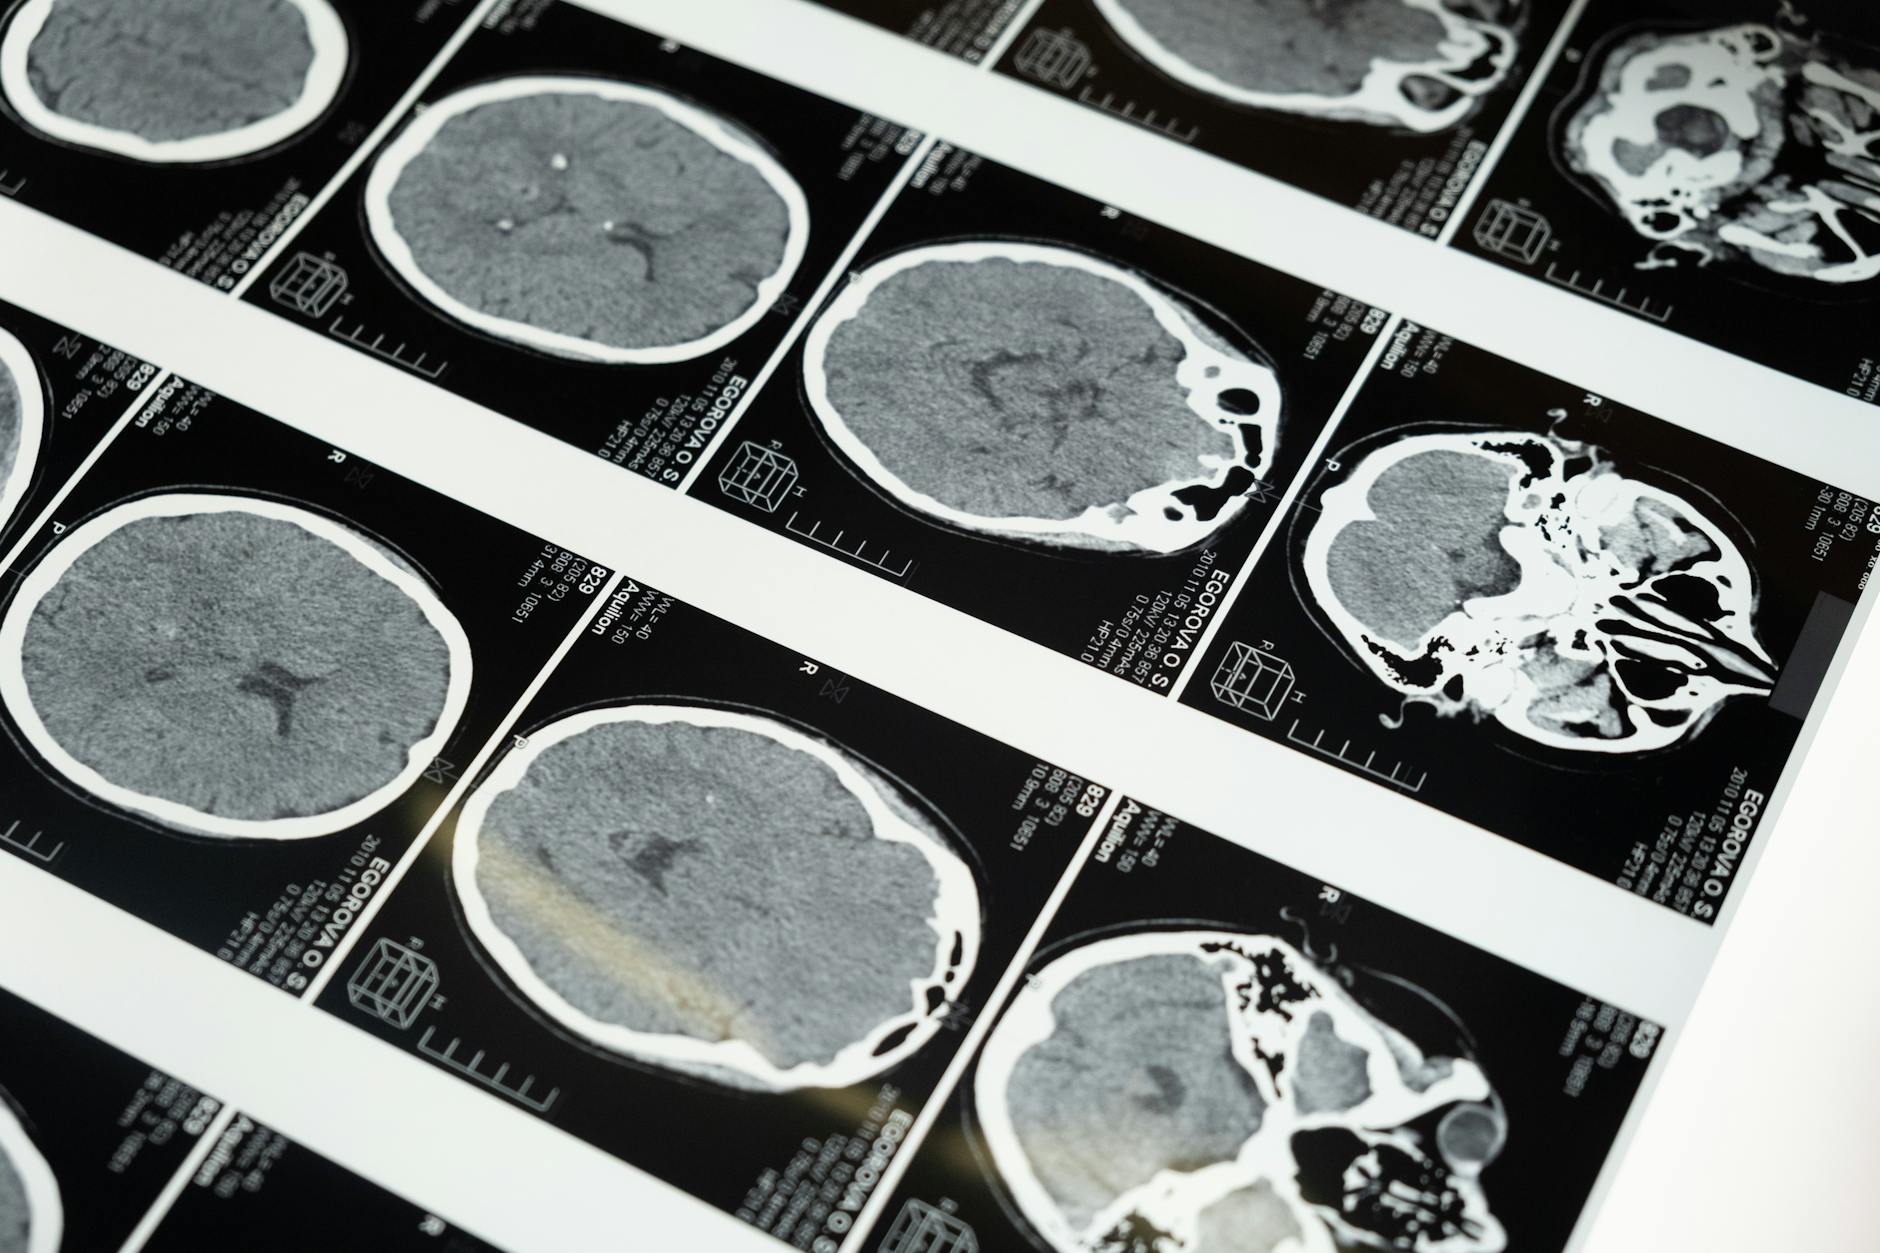

Around 2 million people sustain a traumatic brain injury (TBI) each year.